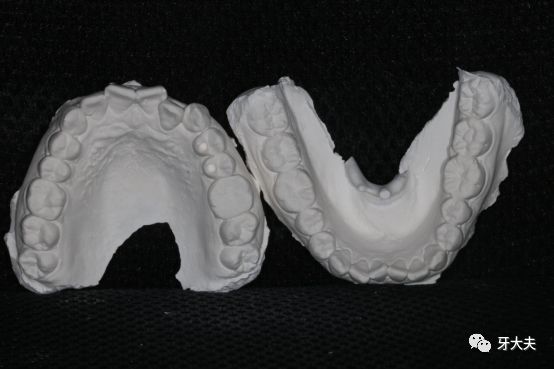

作为一名猪猪女孩,一直被人质疑为什么还要做矫正呢?以前我自己也是这样认为的,从来没想过要整牙,尤其那种钢牙套,还担心牙齿矫正了牙齿会松,牙齿会提前掉,等到自己真正尝试了才发现这些观念都是错的,我做的这一切都是值得的。 先上图。 看牙模更是一目了然这是在牙大夫拍的,是周院长为我看的诊,他说我这属于牙齿不齐,平常自己容易塞牙是有这方面的原因,周院长还和我说,牙齿不齐很容易导致口腔不易清洁,使食物残渣长期滞留,还会容易引起龋齿、牙结石、牙龈炎等,甚至引发牙周病,牙齿松动。